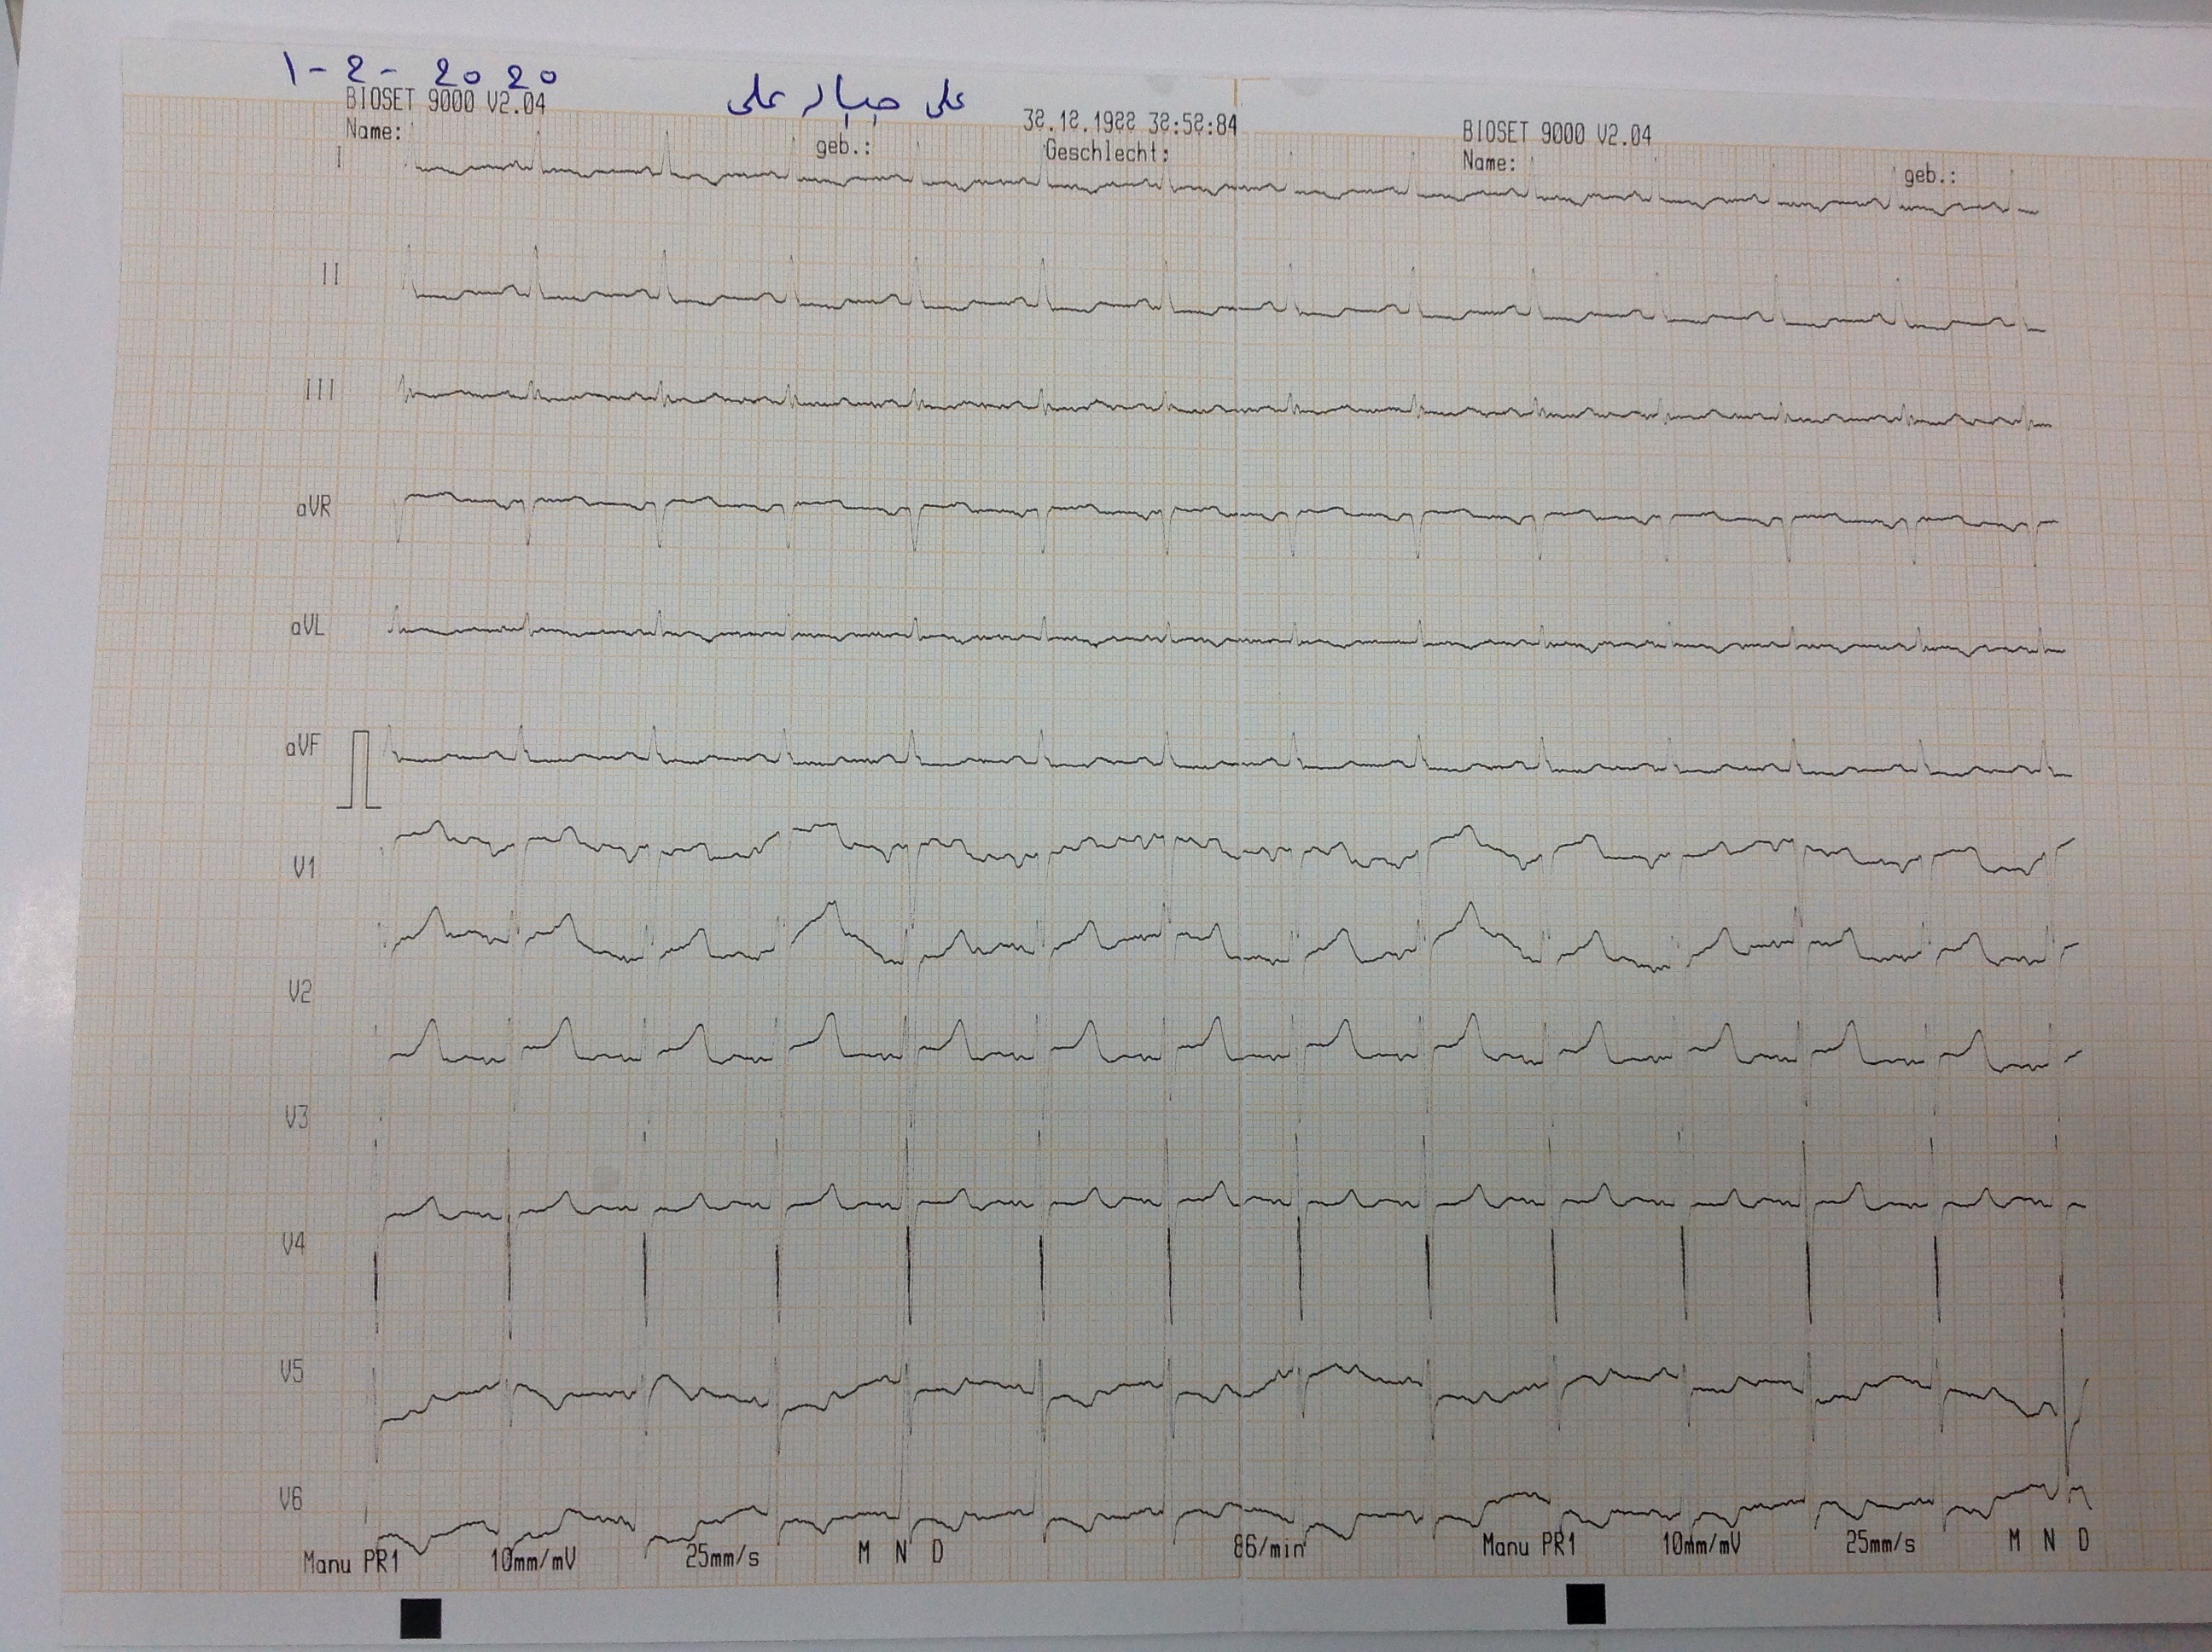

BP : 155/82     PR : 84     RR :     SPO2 : 93     CC : KIDNEY TRANSPLANT

ID : 2065      ALI JABAR JALI           1963             Male      W : kg     H : cm         HTN        IDDM     HPI :